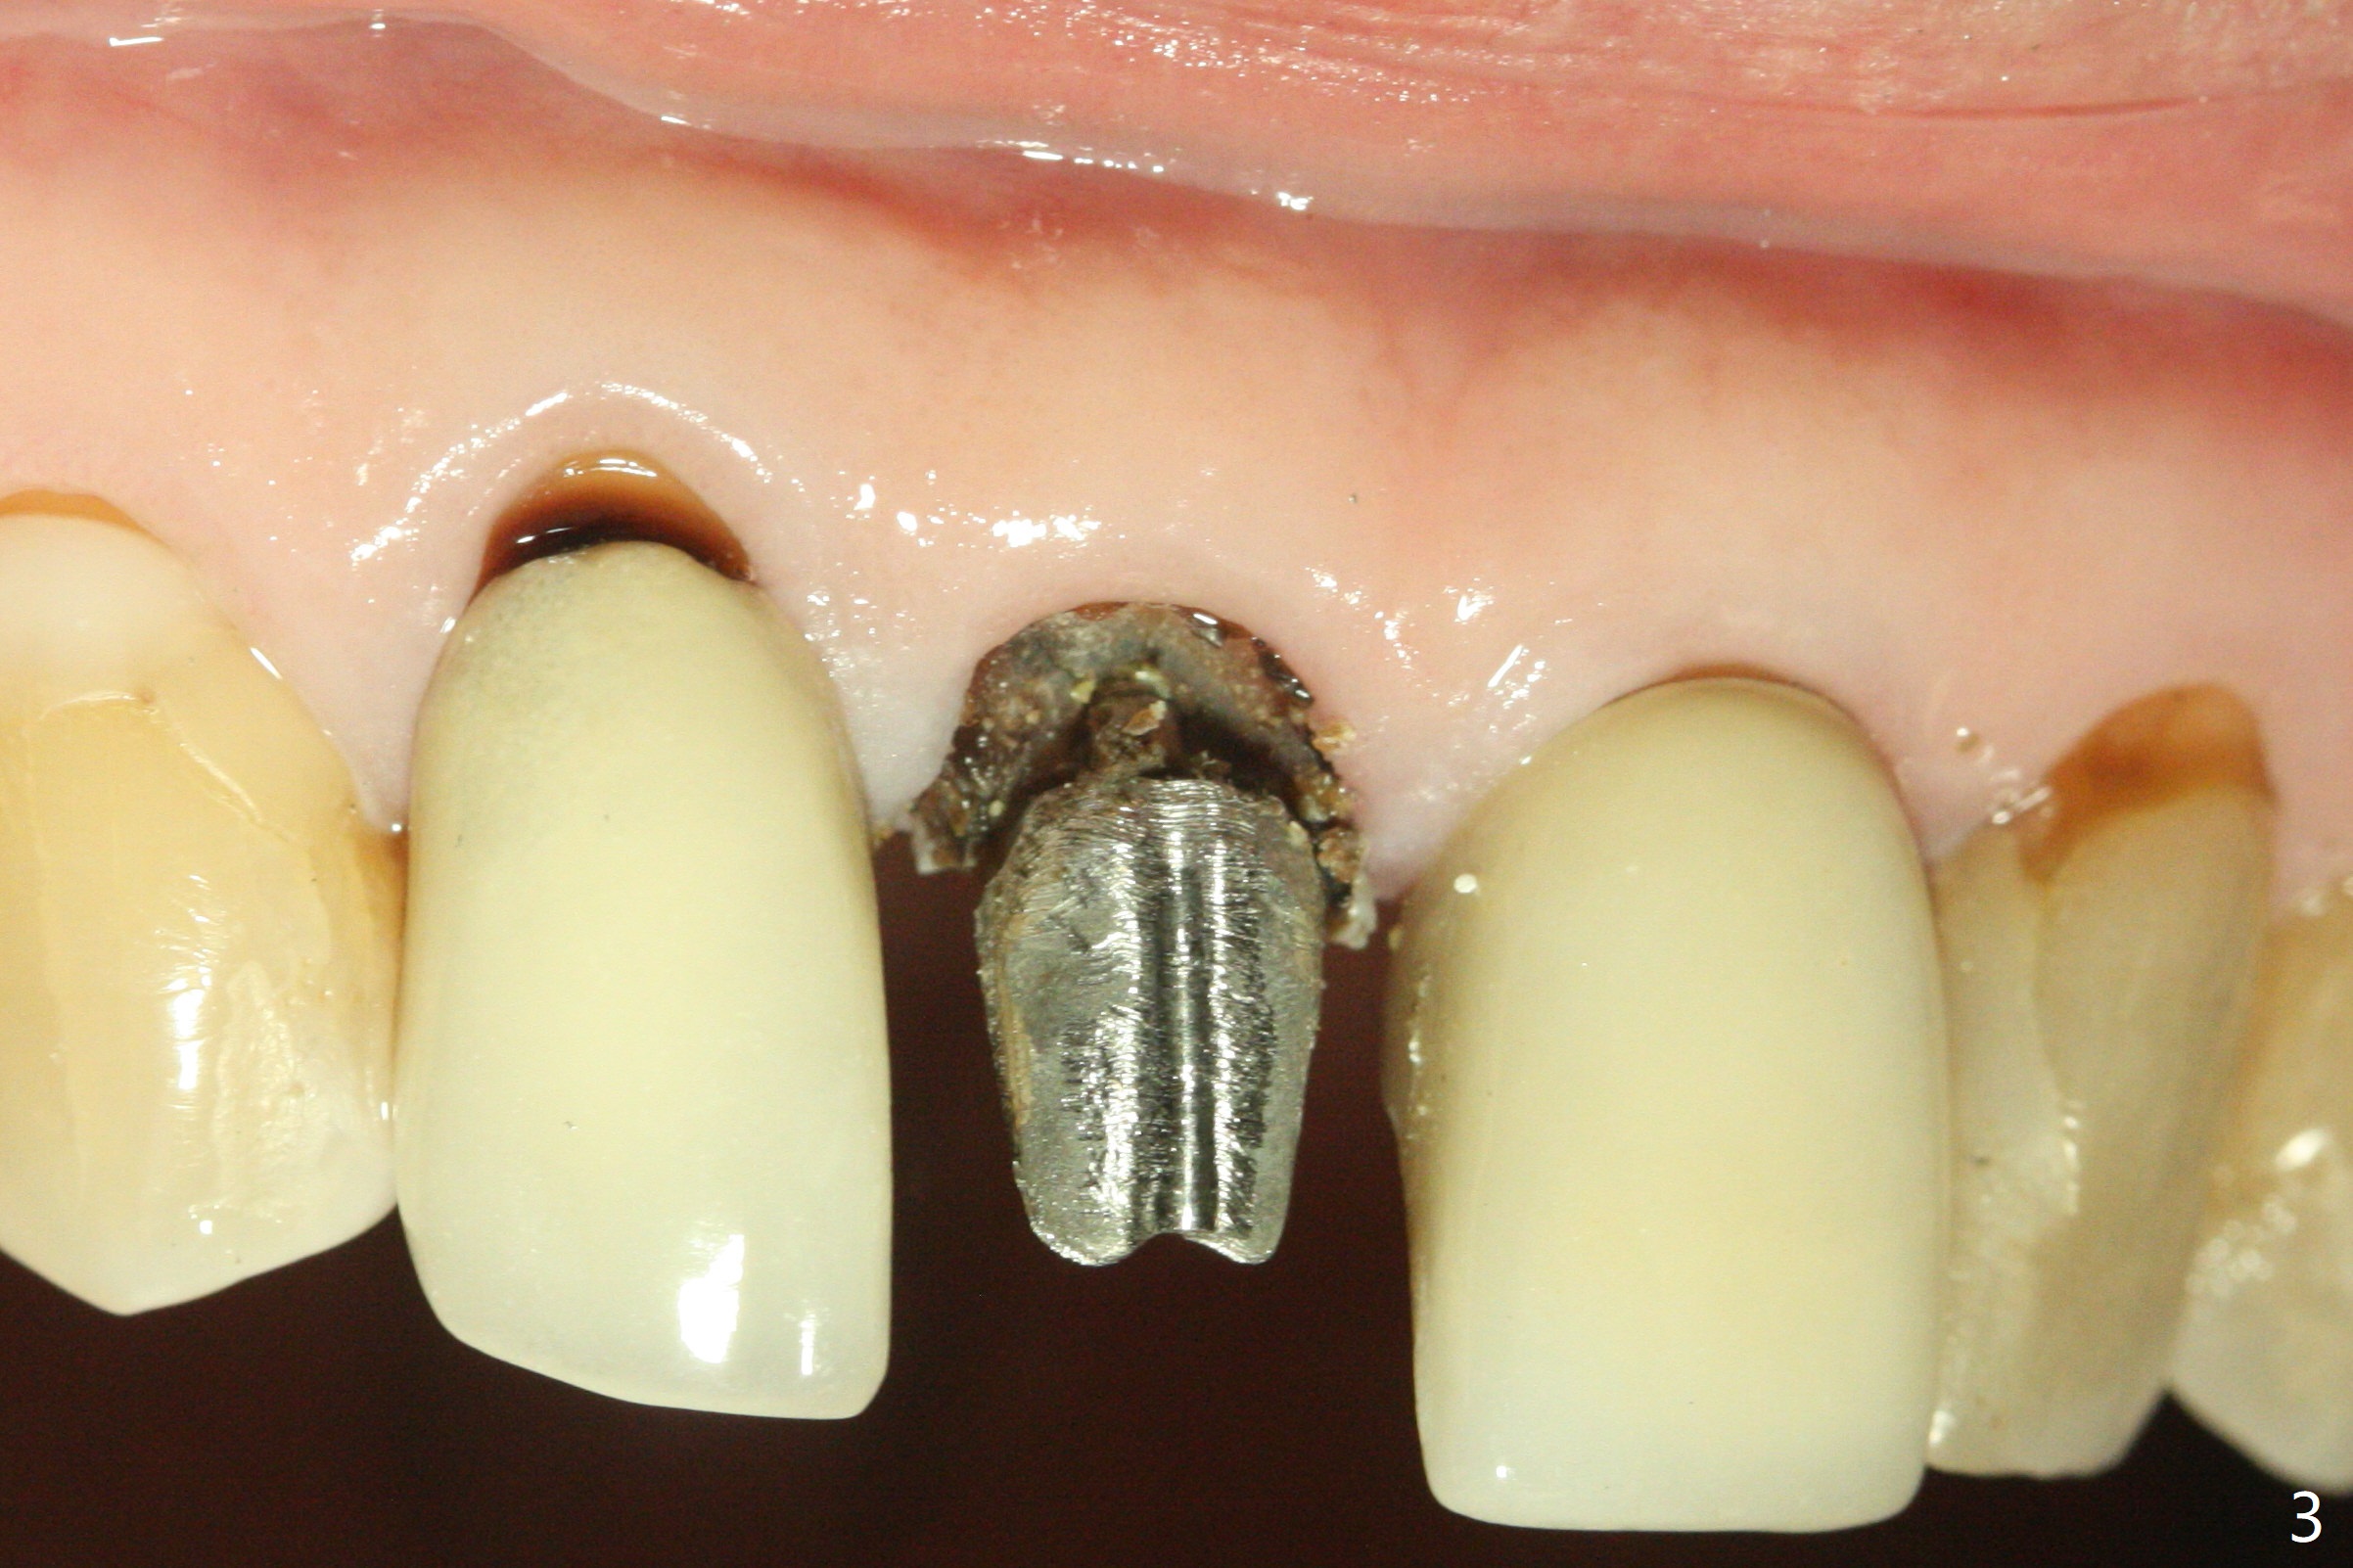

A 66-year-old man returns to clinic for #8 crown redo because of marginal leakage (Fig.1 *). After crown and caries removal, the tooth requires crown lengthening or basically non salvageable (Fig.2,3). For untold reasons, gingivectomy is performed with Waterlase without topical or local anesthesia. Hemostasis is excellent for impression, although there is wide spread of tissue debris from laser (Fig.4 >). The gingiva heals 4 weeks (Fig.5) and 6 weeks (Fig.6) postop.